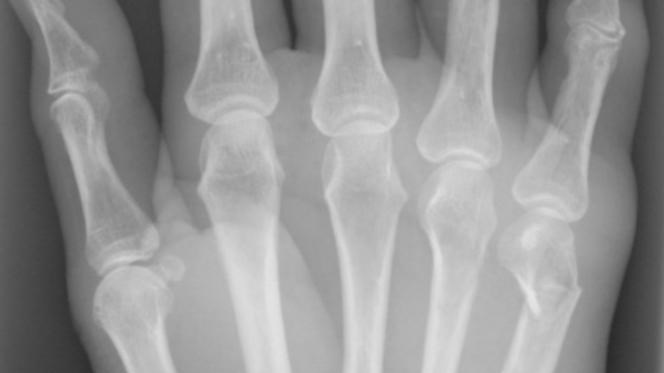

Subcapitulär metacarpalfraktur

Subcapitulär metacarpalfraktur är en vanlig slagsmålsskada och drabbar då ofta metacarpale V. Frakturen dislocerar alltid volart och viss kvarvarande volarställning (ca 30-40° i MCP V) kan accepteras. Behandlas annars med sluten reposition och gips i 3 veckor.

Fingerfalangfraktur

Fordrar vanligen operation p.g.a. att de ofta dislocerar och att det krävs tidig rörelseträning om man skall förhindra att fingret blir stelt.